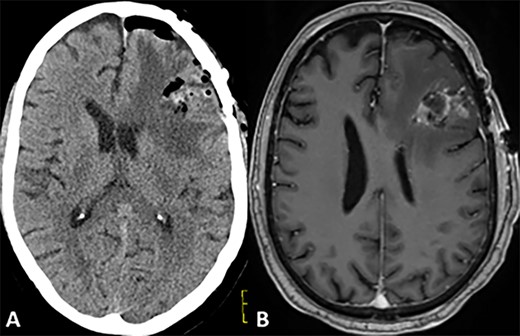

CASE

Postoperative CT and MRI scans of the head indicating complete tumor resection with reduced midline shift.